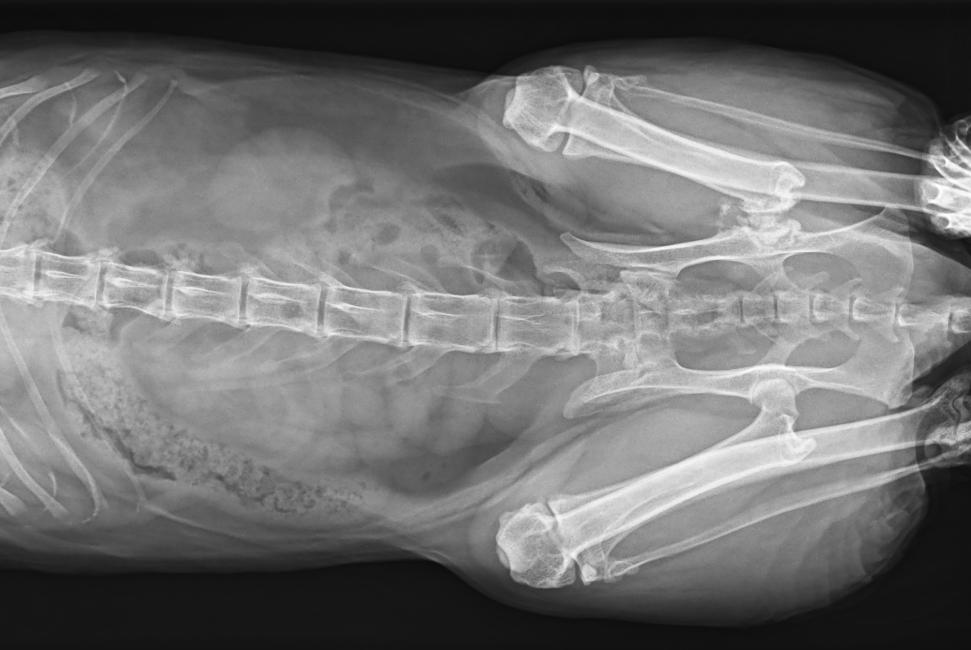

● 17*17大尺寸平板探測器,獲得高質量圖像

● 優(yōu)異的空間分辨率及信噪比,提升圖像質量

● 采用線噪聲消除技術,使成像質量提升40%

● 智能高效的圖像處理軟件,大幅提升圖像質量

● 可浮動床面設計,滿足大部分中小型寵物檢查